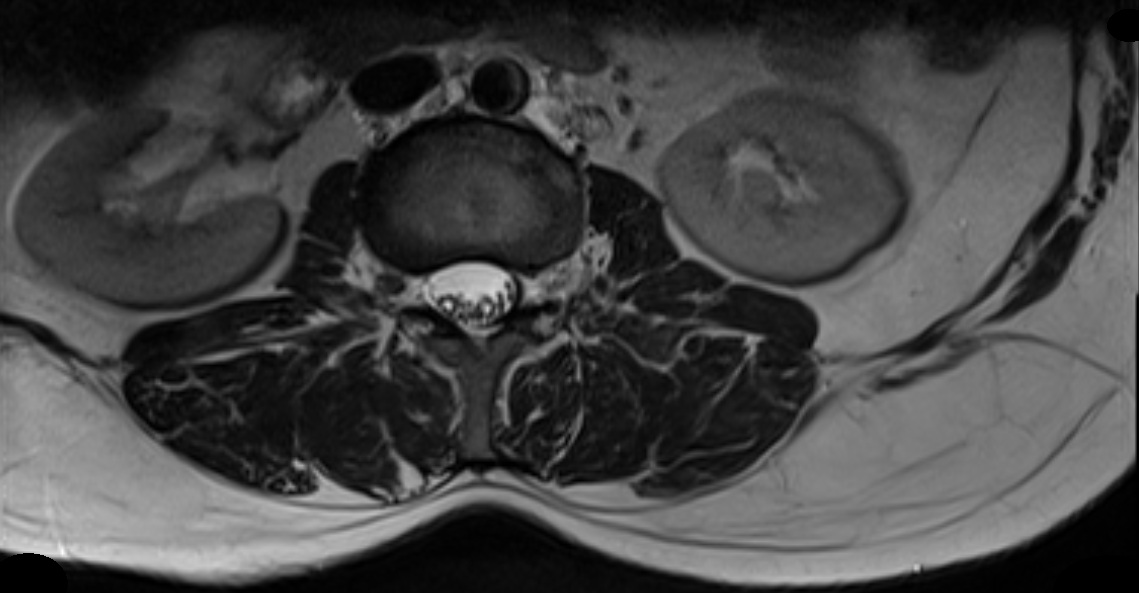

We validated our fast 3D volumetric image reconstruction method on 24 real life T2-MRI data (512×512512512512\times 512 pixels) of human spine with an inter slice gap of 333 to 5mm5𝑚𝑚5mm, and 30 real life T2-MRI data (512×512512512512\times 512 pixels) of human brain collected from Bangur Institute of Neurosciences, S.S.K.M, Kolkata and brain MRI data set of python.

Initially, the 2D2𝐷2D slices are split in 4 sub parts as shown in Figure 2 for a human spine, and the data set in divided in two parts. We use single instruction multiple data architecture using 8 logical cores. In parallel, for each block of sub-image, a 3D3𝐷3D matrix is created which is filled with the corresponding data leaving the specified slice gap in between slices as specified for each set as shown in Figure 3. Then edge preserved kriging interpolation is used to generate the 3d subimages. If we want to visualize these sub-images, then we can apply marching cube with color map and visualize the images as shown in Figure 4 and the complete 3D image for visualisation of full spine is as in Figure 5.

(a) Captured slice #148 along the axial plane for slice sequence of Figure 9a

Refer to caption

(b) Reconstructed slice #148 along the axial plane for slice sequence of Figure 9b

Figure 10: Slice #148 for a human spine along the axial plane for slice sequence of Figure 9b while capture vs after reconstruction